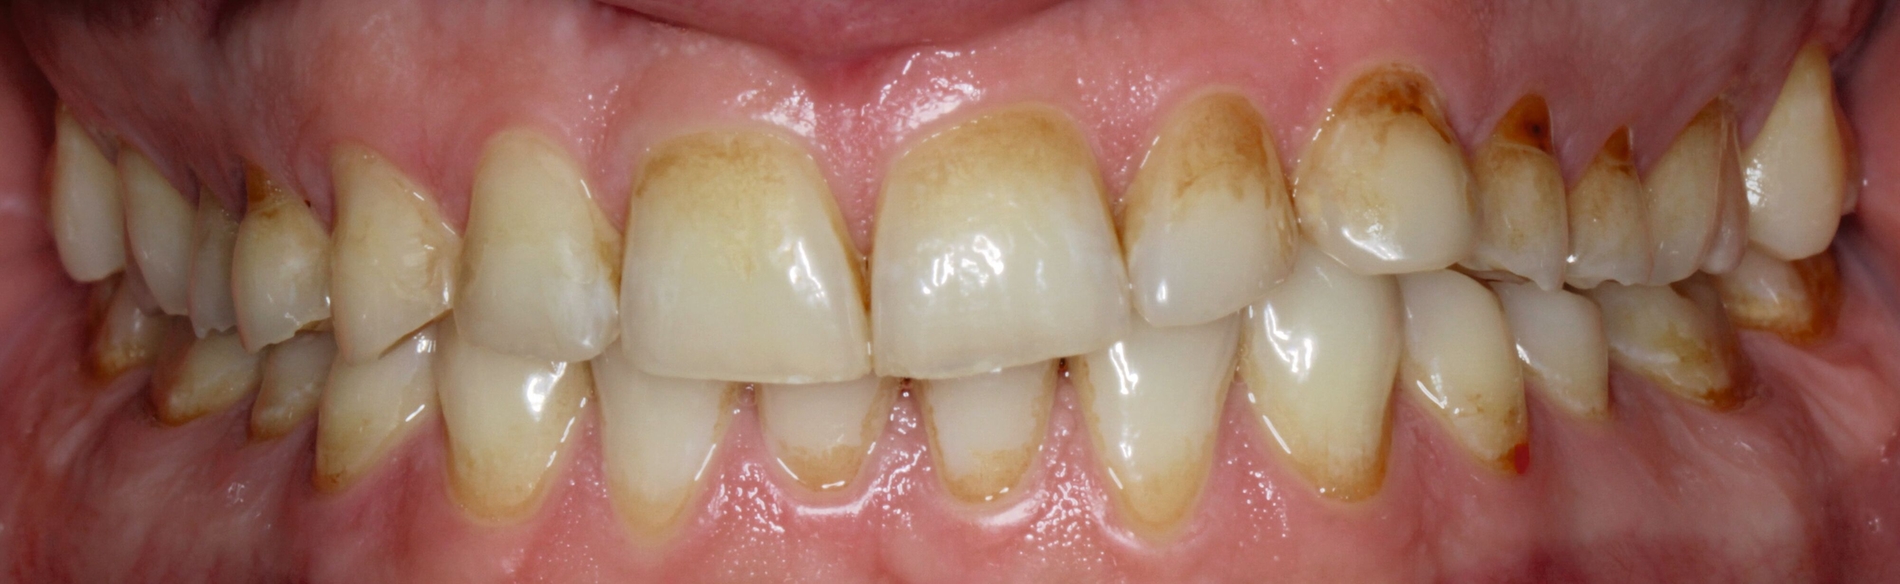

Diagnostik

Klinisch präsentierte sich ein vollbezahntes Gebiss ohne Weisheitszähne mit Defekten an der Zahnstruktur teilweise bis ins Dentin. Es waren deutliche Erosionsspuren zu erkennen, die auf die säurehaltige Ernährung im Kurzzeitintervall zurückgeführt wurden. Der BEWE-Index war mit dem Wert 13 auffällig und kategorisierte den Schaden als ausgeprägte Erosionen. Die Zähne 14, 13 und 24 wiesen nicht-kariöse zervikale Defekte auf, diese treten häufig im Zusammenhang mit Bruxismus auf [Pecie et al., 2011]. Das CMD-Screening der Deutschen Gesellschaft für Funktionsdiagnostik und -therapie (DGFDT) [DGFDT, 2024] war unauffällig, da der Patient über keinerlei Schmerzen oder Beschwerden bei Kieferbewegungen klagte. Die manuelle Strukturanalyse (MSA) nach Bumann [Fasold und Kordaß, 2012] ergab bei diesem Patienten ein myofaziales Schmerzsyndrom. Im Prämolarenbereich imponierten Zahnhartsubstanzdefekte, die Hinweise auf starkes und häufiges Zähnepressen geben. Den Patienten selbst störten seine kälteempfindlichen Zähne sowie die Gesamtästhetik aufgrund des massiven Substanzverlustes.